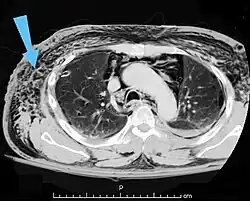

Diagnosis

Significant cases of subcutaneous emphysema are easy to diagnose because of the characteristic signs of the condition.[1] In some cases, the signs are subtle, making diagnosis more difficult.[13] Medical imaging is used to diagnose the condition or confirm a diagnosis made using clinical signs. On a chest radiograph, subcutaneous emphysema may be seen as radiolucent striations in the pattern expected from the pectoralis major muscle group. Air in the subcutaneous tissues may interfere with radiography of the chest, potentially obscuring serious conditions such as pneumothorax.[18] It can also reduce the effectiveness of chest ultrasound.[28] On the other hand, since subcutaneous emphysema may become apparent in chest X-rays before a pneumothorax does, its presence may be used to infer that of the latter injury.[13] Subcutaneous emphysema can also be seen in CT scans, with the air pockets appearing as dark areas. CT scanning is so sensitive that it commonly makes it possible to find the exact spot from which air is entering the soft tissues.[13] In 1944, M.T. Macklin and C.C. Macklin published further insights into the pathophysiology of spontaneous Macklin's Syndrome occurring as a result of a severe asthmatic attack.